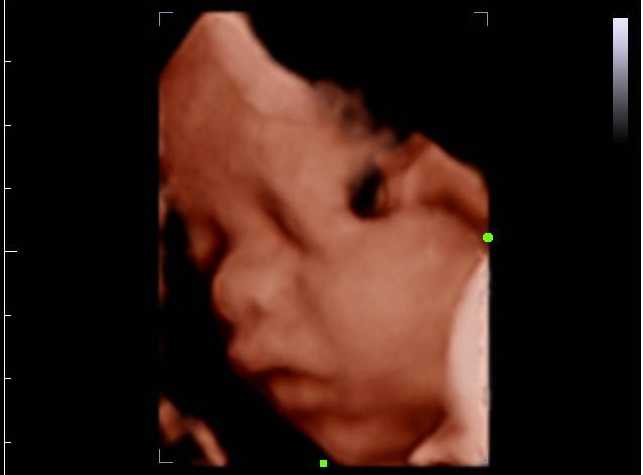

Contoh usg 4 dimensi. Video usg 4 dimensi 2 bagi anda yang ingin download lewat hp dengan format 3gp silahkan download dibawah ini. Seperti halnya penggunaan usg 4 dimensi dimana penggunaan usg 4 dimensi ini sangat membantu untuk mendapatkan objek dari calon anak yang akan terlihat perkembangannya dan biasanya akan terlihat lebih jelas daripada menggunakan usg 3 dimensi. Saya ada rencana pengen usg 4 dimensi. Contoh gambar 4 dimensi janin 5 bulan klik gambar dibawah ini. Setiap jenis usg memberikan hasil yang berbeda beda. Gambaran usg 4 dimensi seperti menonton sebuah film yang bergerak.

Berikut beberapa contoh gambar 4 dimensi. Academiaedu is a platform for academics to share research papers. Hal penting sebelum melakukan usg 4 dimensi. Selain itu ketika kondisi ibu termasuk beresiko dan ada kemungkinan penyimpangan kondisi janin normal tindakan ini seringkali disarankan oleh. Kira kira usia kandungan berapa minggu ya waktu yg tepat. Maksud usg 4 dimensi adalah gambar 3 dimensi yang dapat bergerak.

Usg 4 dimensi bisa membantu biopsi lebih tepat sasaran terutama untuk pemeriksaan tumor payudara prostat hati ginjal dan beberapa jenis tumor yang lain. Selain foto yang saya peroleh saya juga mendapatkan videonya loooohhh untuk teman teman yang ingin tahu bagaimana hasil usg 4 dimensi yang berupa video silahkan download link dibawah ini. Gambaran usg 4 dimensi seperti menonton sebuah film yang bergerak. Maksud usg 4 dimensi adalah gambar 3 dimensi yang dapat bergerak. Dibandingkan usg 2 dimensi dan 3 dimensi sekarang ini ada usg 4 dimensi. Sebetulnya usg 4 dimensi ini hanya istilah untuk usg 3 dimensi yang dapat bergerak live 3d.

Jadi berupa live 3 dimensi. Berikut beberapa contoh gambar 4 dimensi. Jadi pasien dapat melihat lebih jelas dan membayangkan keadaan janin di dalam rahim. Jadi berupa live 3 dimensi. Video usg 4 dimensi 1 2. Kalau gambar yang diambil dari usg 3 dimensi statis sementara pada usg 4 dimensi gambar janinnya dapat bergerak.

Apa bedanya usg 2 3 dan 4 dimensi. Hallo bundas usia kandungan saya skrg 25 minggu lewat beberapa hari. Jenis usg ini mampu menunjukkan gambar yang lebih detil sehingga dokter akan lebih mudah dalam mengidentifikasi masalah pada kehamilan. Kondisi ini dibutuhkan saat dokter ingin mengamati perilaku janin fetal behavior lebih jauh. Contoh gambar 4 dimensi janin 5 bulan klik gambar dibawah ini.